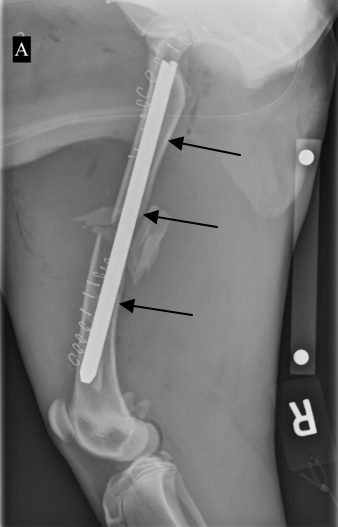

이 X-ray 이미지는 다리의 뼈에 철심이 잘 고정되어 있는 모습을 보여줍니다.

이 이미지에서도 보듯이, 다리의 뼈에 삽입된 로드는 뼈의 정렬을 도와줍니다. 이런 방식으로 뼈가 정상적으로 회복될 수 있도록 지원합니다.